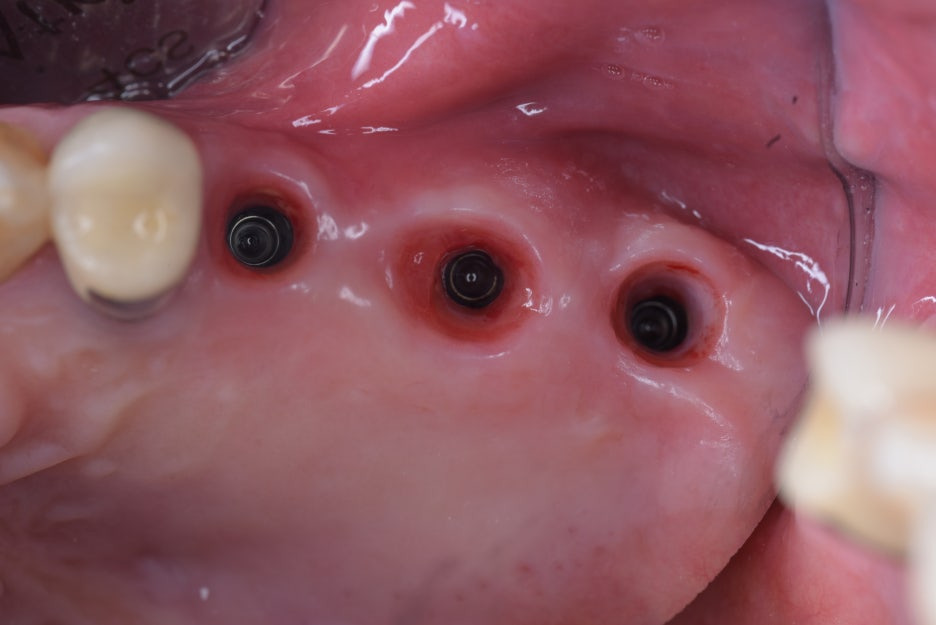

[ 임플란트 2차 수술 후 ]

충분히 시간이 지난 뒤 임플란트 2차수술을 통해서

잇몸 안에 묻어둔 임플란트에 단추를 달아서 치아를 만들 수 있게 준비를 합니다.

좁아져있던 처음 잇몸보다 잇몸의 형태와 양이 개선된 상태입니다.